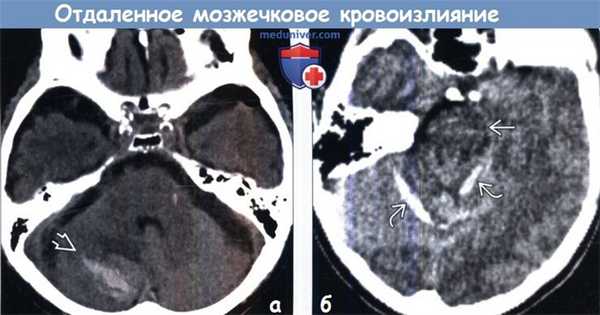

(а) КТ, аксиальный срез: у молодого пациента, которому была выполнена левосторонняя височная лобэктомия, определяется острое кровоизлияние в правое полушарие мозжечка - отдаленное мозжечковое кровоизлияние (ОМК). Предположительная этиология-ликворная гиповолемия, которая привела к нисходящему смещению мозжечка и вторичному повреждению венозных структур.

(б) MPT, GRE, аксиальный срез: у пациента с ОМК определяется типичный артефакт восприимчивости или участки «выцветания» изображения, отражающие отдаленное кровоизлияние. Кровоизлияние может быть одно-, двусторонним или изолированным от червя мозжечка. (а) КТ, аксиальный срез: у пациента 86 лет, которому была выполнена левосторонняя трепанация черепа с постановкой катетера для дренирования левой субдуральной гигромы, определяется правостороннее ОМК. Это кровоизлияние было выявлено случайно. Большинство пациентов с ОМК нуждаются в оперативном вмешательстве.